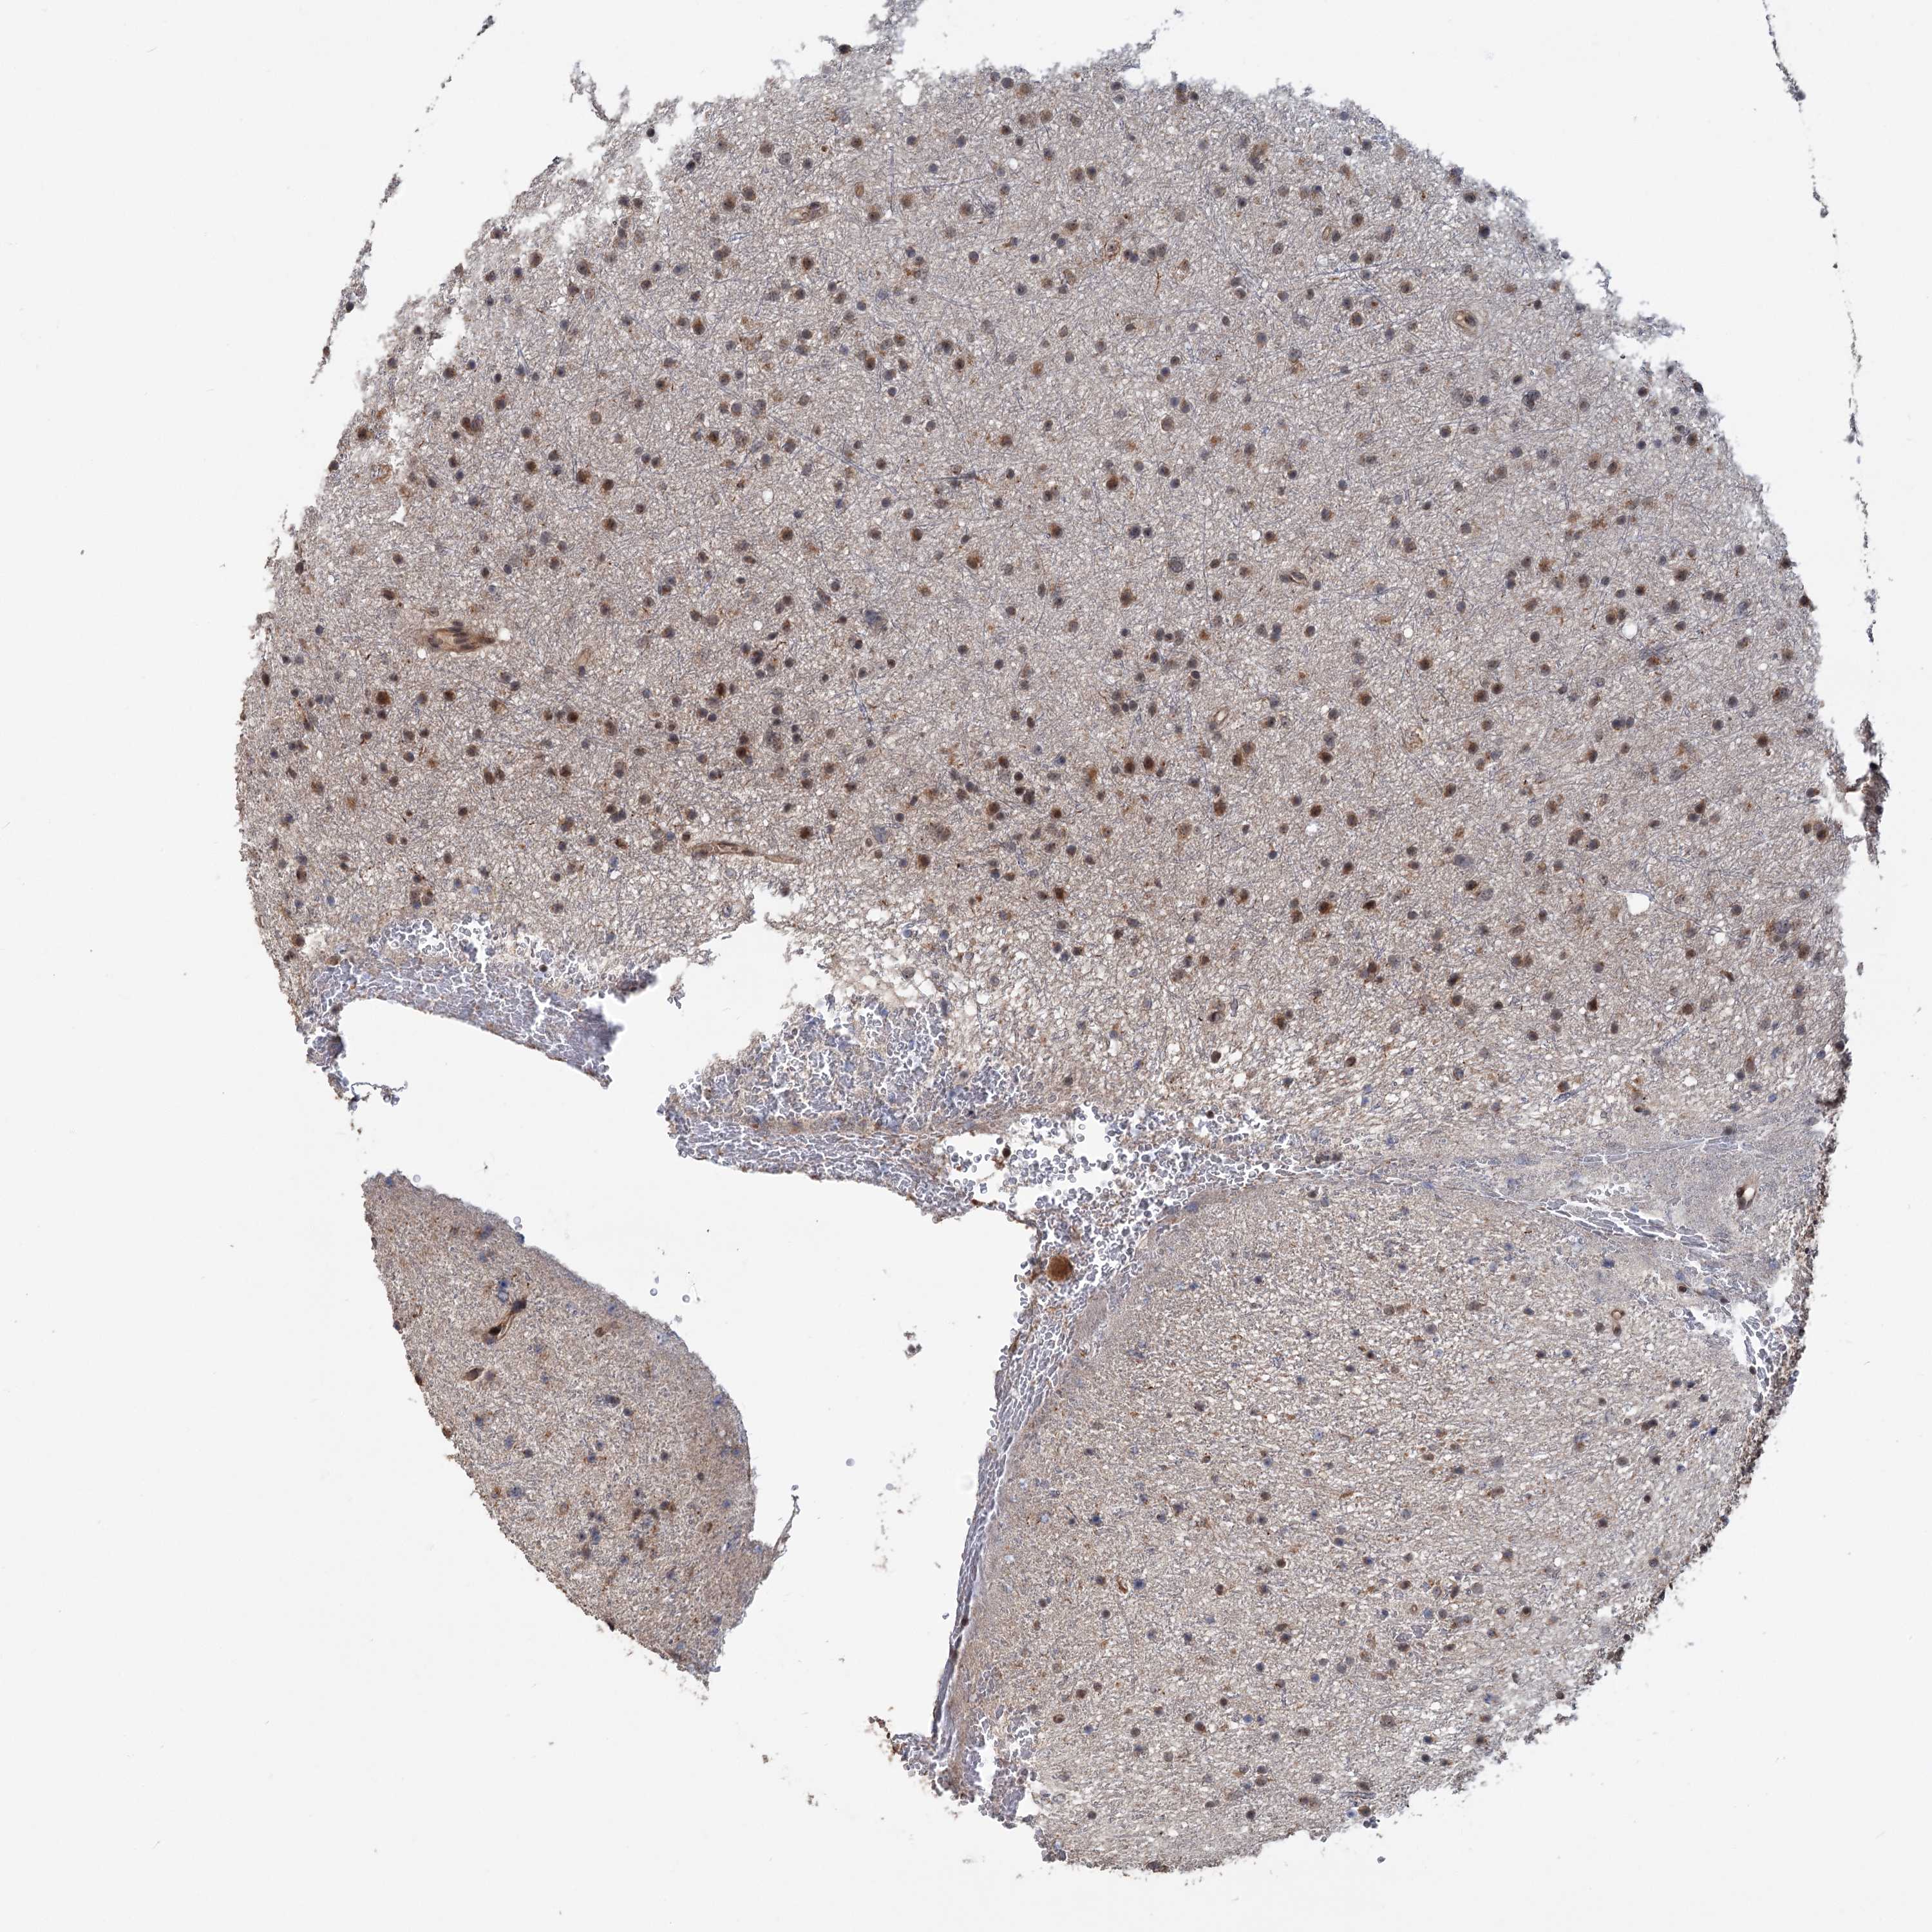

GLIOMA - Protein expressioni

A mouse-over function shows sample information and annotation data. Click on an image to view it in a full screen mode. Samples can be filtered based on level of antibody staining by selecting one or several of the following categories: high, medium, low and not detected. The assay and annotation is described here.

Note that samples used for immunohistochemistry by the Human Protein Atlas do not correspond to samples in the TCGA dataset.

Antibody stainingi

Antibody staining in the annotated cell types in the current human tissue is reported as not detected, low, medium, or high, based on conventional immunohistochemistry profiling in selected tissues. This score is based on the combination of the staining intensity and fraction of stained cells.

Each image is clickable and will lead to virtual microscopy that enables deeper exploration of all samples and also displays staining intensity scores, fraction scores and subcellular localization as well as patient and tissue information for each sample.

Antibody HPA038497

Antibody HPA038498

Staining

High

Medium

Low

Not detected

Intensity

Strong

Moderate

Weak

Negative

Quantity

>75%

75%-25%

<25%

None

Location

Nuclear

Cytoplasmic/membranous

Cytoplasmic/membranous,nuclear

Glioma, malignant, High grade

Glioma, malignant, Low grade